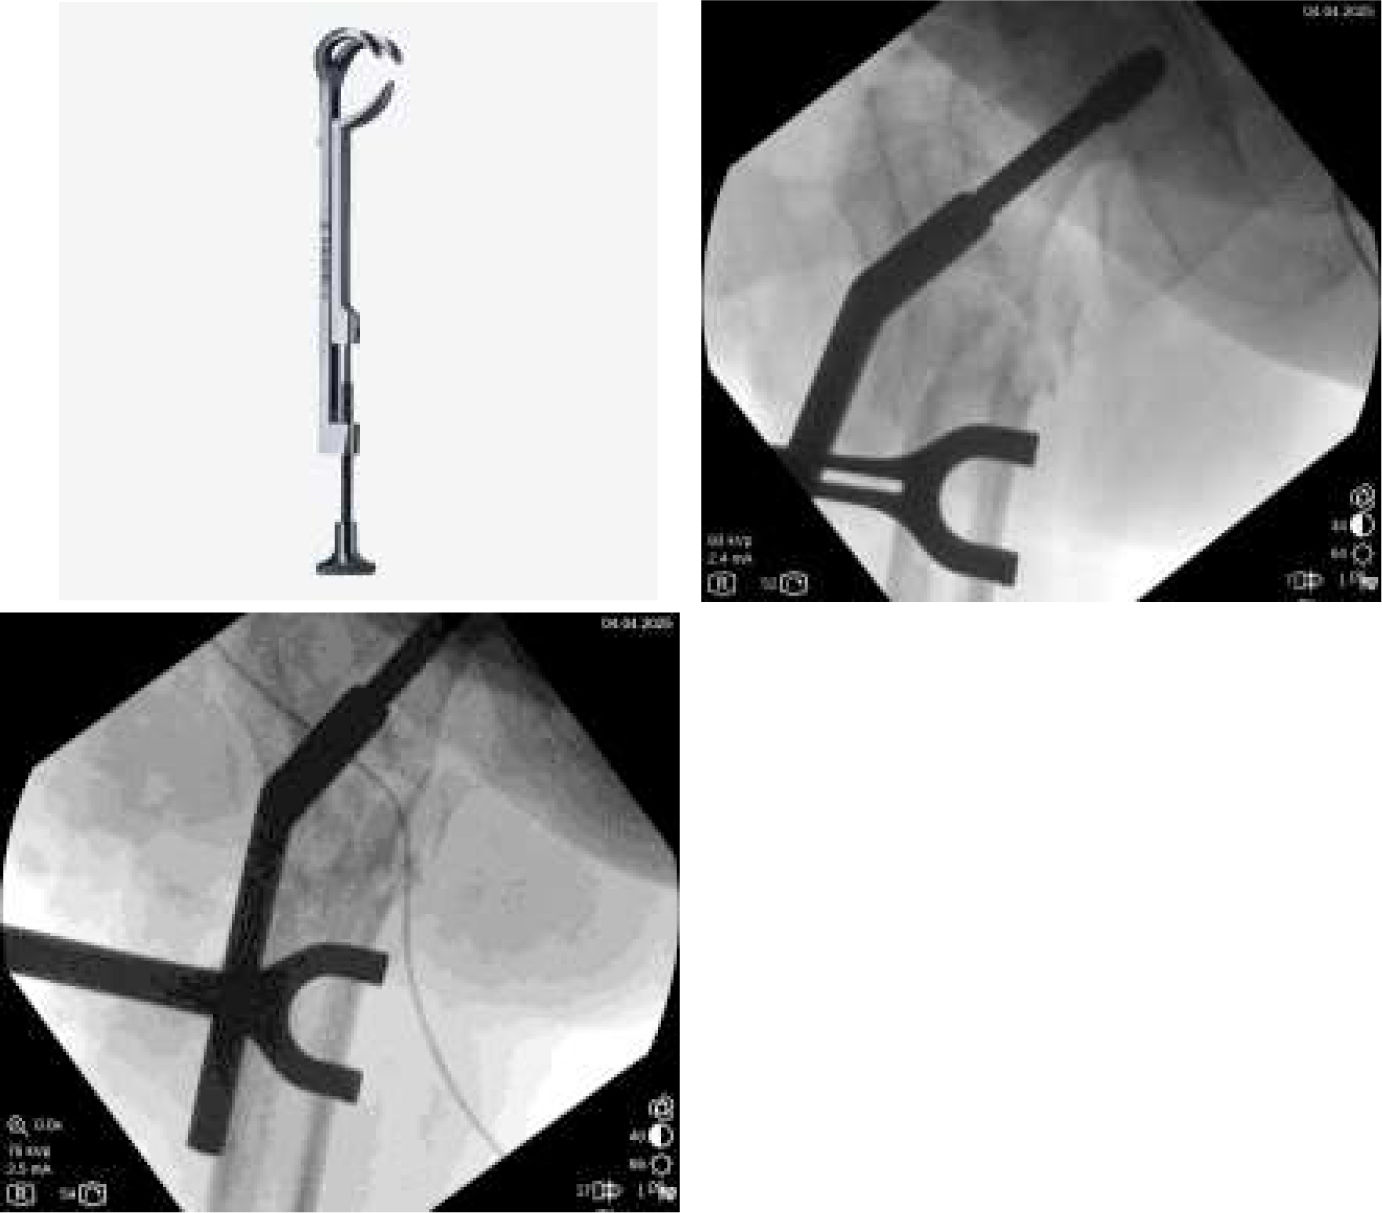

The plate to use should be a DHS (dynamic hip screw, several trademarks sell it), with at least 6 holes, and an angulation of 135–150°.

Head preparation: filling the void and insertion of the cephalic screwThere is a void in the previously retrieved cephalic screw of the blade. This void is worth filling to get a better purchase of the new screw. A 40-gr stick of allogenic trabecular bone is prepared as follows: the width of the previous hole is measured, and a trephine is used to get a barrel of the same width (Fig. 4). This is impacted in the hole with an impactor.

As previously planned, the guidewire is inserted in the femoral head as deeply as possible to get into the hard bone of the femoral head. After drilling, a cephalic screw of correct length is inserted.

Over-valguization of the nonunionIn this moment, the DHS (of at least 6 holes) is introduced to the previously introduced cephalic screw. To correct the position of the femoral head, the plate should be placed just over the diaphyseal bone. To accomplish this, a Lowman retractor is recommended. Softly, the retractor is tightened, and the plate comes to the diaphyseal bone, reducing the nonunion (Fig. 6).